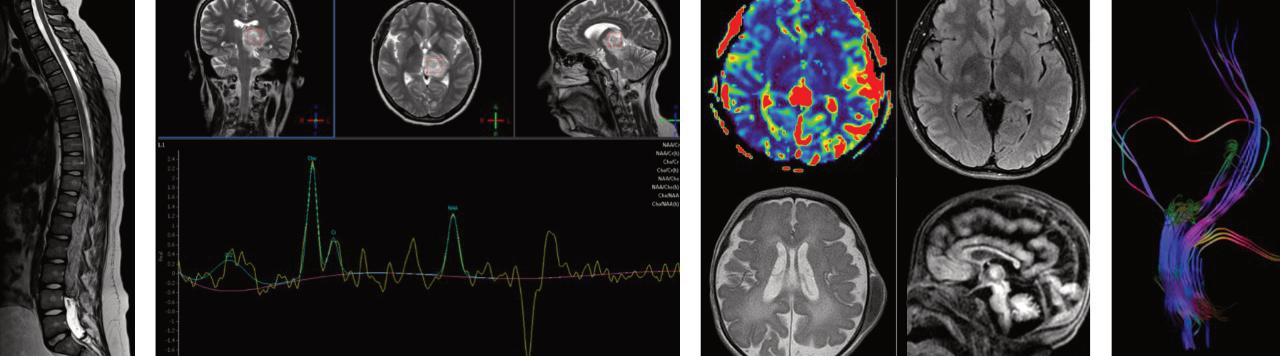

MédicoRadiólogoconespecialidadenNeurorradiología,egresadadelInstitutoNacionaldeNeurologíayNeurocirugía “ManuelVelascoSuárez'',certificadaporelConsejoMexicanodeRadiologíaeImagenA.C. MaestraenCienciasMédicasyvocaldelComitédeÉticaenInvestigación.

Comomédiconeurorradiólogoestoy encargadadeldiagnósticodelas enfermedadesdelsistemanervioso central,esdecir,delaspatologíasdelencéfa‐loyraquimedulares.

Elabordajeneurorradiológicoesmuyamplio, conlosdiferentesmétodosdeimagenana‐lizamosmalformacionescerebrales, alteracionesvasculares,tumores,enferme‐dadesdesmielinizantes,patologíasinfec‐ciosasytrastornosneurodegenerativos.

Encadaetapadelavidaeltipodeenferme‐dadesqueafectanalsistemanerviosocentral varían,porlotanto,miabordajediagnóstico incluyedesdepacientespediátricoshasta adultosmayores.

Actualmente,lastécnicasdeneuroimagen nospermitenirmásalládedecirqueexiste una“tumoracióncerebral”;esdecir,podemos

hacereldiagnósticodiferencialdelesiones infecciosasopatologíasconlesiones“pseu‐dotumorales”sinnecesidaddetenerque llegaralatomadebiopsia.Además,enelcaso delostumorescerebrales,lastécnicasde perfusiónyespectroscopíaporresonancia magnéticanosayudanadiagnosticarelorigen yelgradodeltumor.

Untema,queenlopersonal,meapasionamu‐choeseleventovascularcerebraloinfarto cerebral,porqueesunapatologíaenlacualel diagnósticotempranoyelanálisisneuro‐rradiológicoinfluyeneneltratamientooportuno ylaevolucióndelpaciente,conlastécnicasde perfusiónportomografíaoresonanciamagné‐ticapodemosanalizareltejidodepenumbra,es decir,eltejidocerebralqueestásufriendoporla faltadeoxígenoyquesepuedesalvarsidamos untratamientooportuno.

EnelCentrodeDiagnosticoIntegralcontamos conunequipodetomografíaquenospermite realizardesdeunestudiosimple,hastaestudios deperfusiónportomografíayangiotomografía cerebral.Además,contamosconunareso‐nanciamagnéticade1.5Teslaquetieneelso‐ftwaredeneurorradiologíaparapoderrealizar secuenciasavanzadascomoperfusión,espec‐troscopíaytractografía.Mifunciónescrearysu‐pervisarelprotocolodeestudioparacadatipo depatologíaypaciente,mimisiónesllegaral diagnósticoneurorradiológicoencadacaso, haciendousodetodaslasherramientasconlas queactualmentecontamos,paraquecada pacientepuedarecibiruntratamientooportuno.

TodoslospacientesqueacudanalCDIpueden estartranquilosysegurosdequecontamos conlosmejoresequiposyelpersonalcapaci‐tadopararealizarestudiosdeneuroimagen sinnecesidaddeacudiraotrosestados.